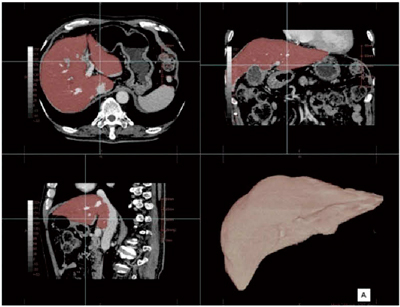

■肝臓解析(W.I.P.)

肝臓移植手術などの術前シミュレーションや肝実質の体積評価のための肝臓解析ソフトの開発にも取り組んでいる。オートセグメンテーション機能により,肝臓を抽出して領域ごとに表示する(図6)。

図6 オートセグメンテーションによる肝臓抽出